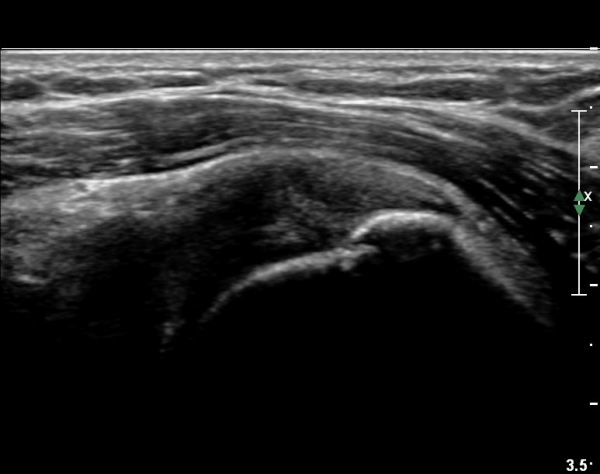

ÃÊÀ½ÆÄ °Ë»ç

´ë°áÀý°ú °ßºÀÇϺο¡ ¹æ»ç¼± Åõ°ú¼º °¨¼Ò(sclerosis)°¡ °üÂûµÈ´Ù(÷ºÎÆÄÀÏ).